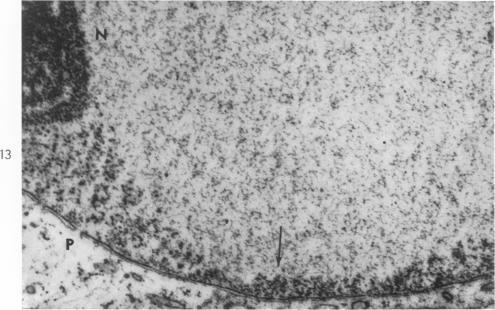

Fine structure of cellular inclusions in measles virus infections.

J Biophys Biochem Cytol. 1959 Dec;6(3):379-82. doi: 10.1083/jcb.6.3.379.